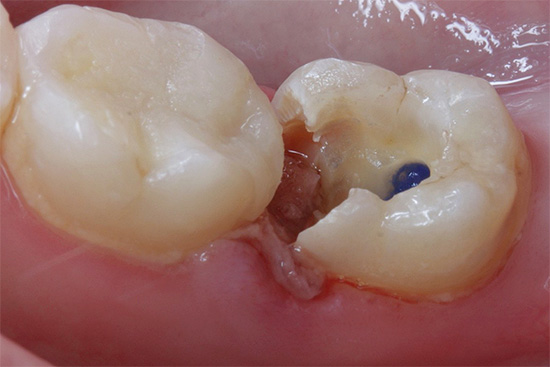

Também deve ser observado o tratamento de cárie superficial e profunda com uma técnica de preenchimento. Quando se trata de cavidades subgengivais, surge uma situação difícil: a incapacidade de isolar um local para um futuro preenchimento bem de saliva, fluido gengival, sangue, etc.

Como resultado, o médico protege cuidadosamente a gengiva contra danos desnecessários: pode realizar diatermocoagulação (remoção do excesso de gengivas com uma ponta aquecida a altas temperaturas), retração (correção de bordas salientes) das gengivas com fios especiais embebidos em uma solução hemostática. Todo o procedimento é realizado, é claro, com boa anestesia para alcançar ótimos resultados finais no tratamento de cárie radicular.

O tratamento da cavidade é realizado sob o resfriamento com água do dente, uma cavidade oval limpa de cárie e a infecção é formada mais frequentemente com áreas adicionais para melhor fixação dos futuros recheios. É tratado com anti-sépticos e selado.

Atualmente, a complexidade da escolha de um material para preenchimento está associada a diferentes tipos de localização da cavidade, sua forma, presença de vários fatores interferentes: saliva, sangue, fluido gengival etc. É difícil colocar o material “seco” e o compósito moderno (“leve”) recheios são muito sensíveis ao ambiente úmido.